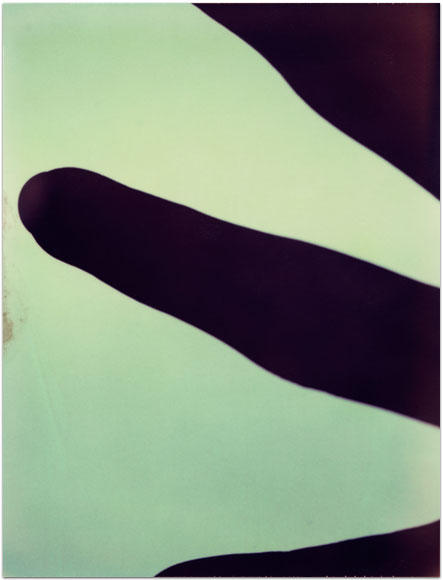

- Itis

- 2004

- 3.25″ × 4.25″

- Photographic montages of my hands & health paraphernalia on Polaroid Type 664 & 669 Film using a Daylab Printer.

- Frustrated by a lack of mobility and severe pain with my fingers, unable to accomplish any task requiring joint dexterity,

I noticed piles of health related papers strewn around. I layered these in a slide printer without removing

my hands, enlarging both onto the film.